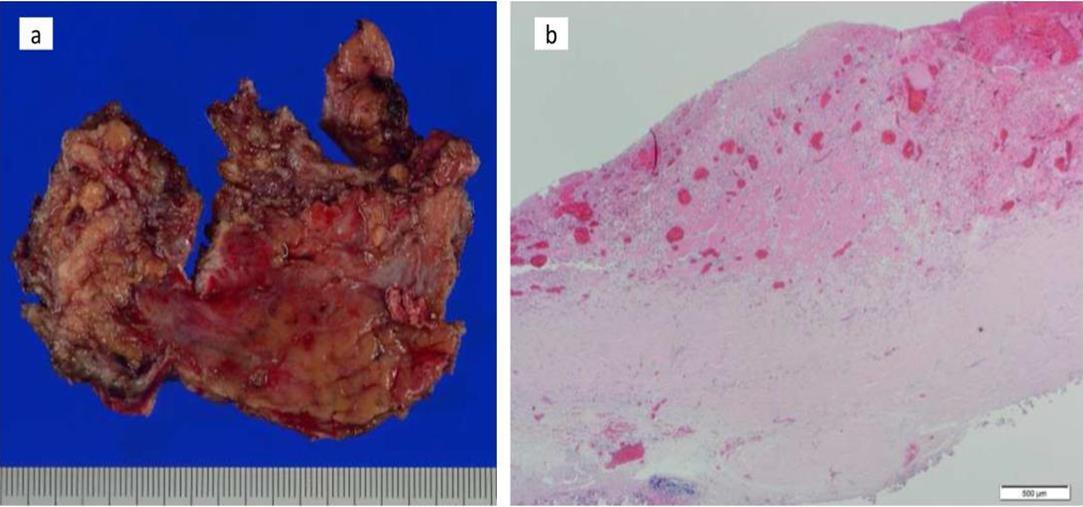

At the age of 52 years, the patient was admitted to our institution for both evaluation of heart failure and regular right heart catheterization including EMB. With respect to allograft rejection, ACR was again detected on regular EMB, and the immunosuppressive regimens were strengthened. Further echocardiographic investigations were conducted to explore the implications of findings indicative of constrictive physiology with thickened pericardium. Respiratory variation in both mitral and tricuspid inflow velocities was seen, but these findings did not meet the complete criteria for CP diagnosis (Figure 1c-e). Magnetic resonance imaging of the heart revealed seroma and a thick cystic-like capsule tightly adhered to the right ventricle (Figure 2a, b). Right heart catheterization revealed elevation of right atrial pressure with severely reduced cardiac index (Figure 3a). The classic dip-and-plateau pattern of right ventricular diastolic pressure and equalization of right atrial pressure and right ventricular diastolic pressure were also observed (Figure 3b). Based on these results, effusive CP or cardiac tamponade-like hemodynamics were strongly suspected, although the etiology remained unknown. Therefore, at 3 years post-HTx, the patient initially underwent removal of the seroma through exploratory lateral thoracotomy to elucidate the etiology of the disease. Yellowish fluid was found and the fluid was completely aspirated. Immunosuppressive regimens including everolimus, which may interfere wound healing, were temporarily converted to standard three-drug regimens. Removal of the seroma via lateral thoracotomy did not lead to improvement in symptoms or hemodynamics. Pathological analysis revealed fibrin and seroma, but no malignant cells or infection. Since the initial procedure did not have any effect on the patient’s symptom, pericardiectomy through median sternotomy was performed at two months after the initial procedure. Intraoperative findings indicated a thickened pericardium and effusion in front of the right ventricle. At first, after sternotomy and adhesiotomy, the tissue in front of the right ventricle, which appeared to be thickened parietal pericardium, was completely resected and the effusion fluid was removed. However, high central venous pressure (20 mmHg) persisted, resulting in a displacement of the left ventricle by the right ventricle. Therefore, additional tissue from the front of the right ventricle was excised, corresponding to diffusely thickened visceral pericardium and epicardium. After the procedure, central venous pressure decreased from 20 to 10 mmHg, and displacement of left ventricle resolved. Pathological analysis of the resected tissues demonstrated chronic fibrosis and chronic inflammation with plasma cells, but no infectious etiology was identified (Figure 4 a, b). After the pericardiectomy, hemodynamics (Figure 3a, c) and symptoms improved, and the patient is currently experiencing a favorable clinical course without complications.

Figure 4.Pathology findings. Chronic fibrosis and chronic inflammation with plasma cells were seen, but no infectious etiology was identified in resected tissues (a. macroscopic; b. microscopic)